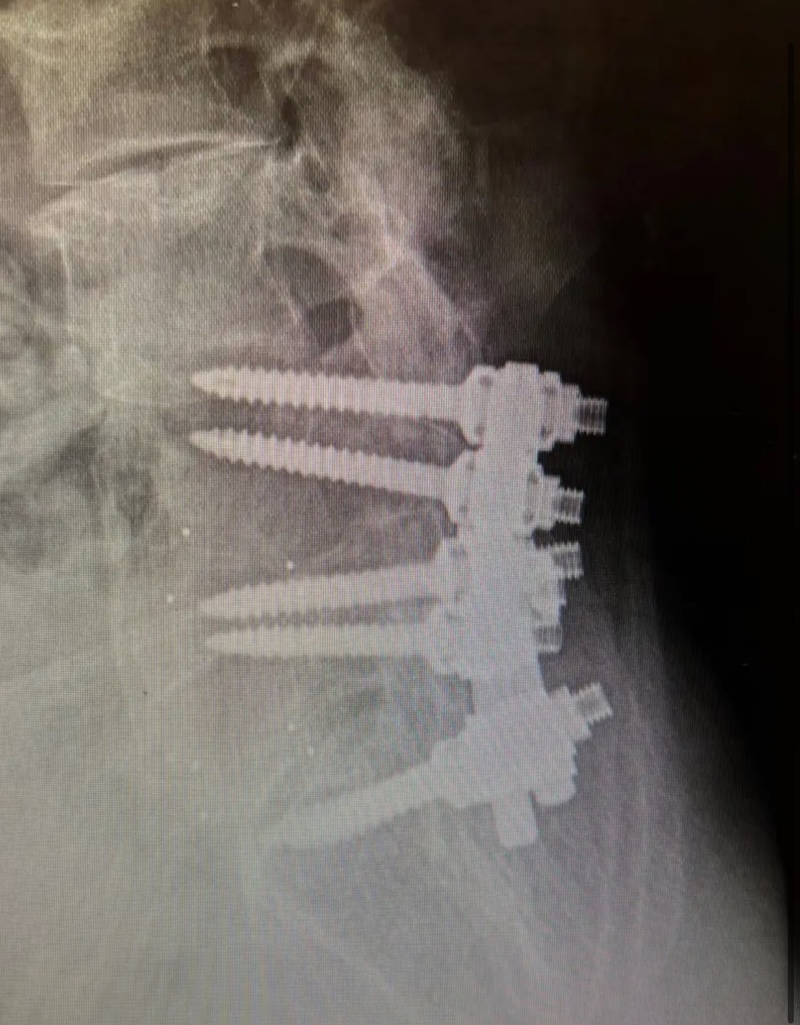

DePuy Monarch Offset Pedicle Screw System (Historical)

Product Category: Spinal Implants , Historical Products

Screw Type: Pedicle Screws (Thoraco-lumbar)

By Location/Approach: Posterior Thoracic , Posterior Lumbar

By Procedure Type: Thoraco-lumbar-Pelvic Fixation

The MONARCH Spine System was originally produced by DePuy and is a titanium thoracolumbar pedicle screw fixation system. It is characterized by the pedicle screw with a polyaxial offset plate.